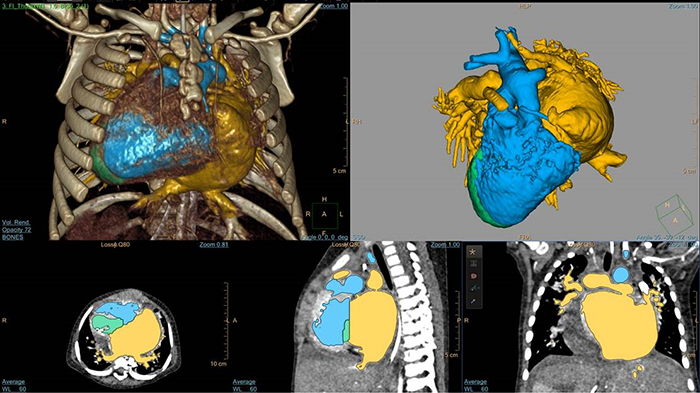

Modelado 3D con IntelliSpace Portal

Flujo 4D de IntelliSpace Portal MR Caas en tetralogía de Fallot